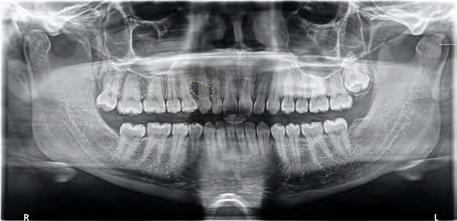

A 25-year-old female, in apparent good health, presented to an oral surgeon with referral from a general practitioner for evaluation of an incidentally discovered lesion of the maxilla. A review of her medical history was noncontributory, and the extraoral and intraoral examination was unremarkable.

Panoramic radiograph revealed a single, unilocular radiolucency between her right maxillary canine and premolar (Figure 1). A biopsy of the radiolucent lesion was performed to establish a diagnosis. Microscopic examination revealed islands of bland squamous epithelium (Figure 2a) with occasional microcyst formation (Figure 2b). Calcified bodies were noted in some of the islands. Based on these findings, a diagnosis of squamous odontogenic tumor was rendered.

Clinically, patients with SOT present with asymptomatic swelling, mobility of the adjacent teeth and localized periodontal bone loss. The tumor is often associated with erupted, vital teeth and is commonly discovered incidentally on routine radiographic examination. Radiographically, the tumor has a characteristic appearance of a triangular unilocular radiolucency between the roots of two teeth, with the base of the triangle toward the root apices; rarely, does SOT appear as large, multilocular lesions.[4] When considering a unilocular radiolucency in the maxilla, multiple differential diagnoses must be considered.

Figure 1. Panoramic radiograph demonstrates well-defined, unilocular radiolucency between right maxillary premolar and canine. Figure 2. (b) Occasional cyst formation is noted in some of islands (400x magnification).

Figure 2. (a) Hematoxylin-eosin stain of biopsy specimen consists of islands of bland squamous epithelium (100x magnification).